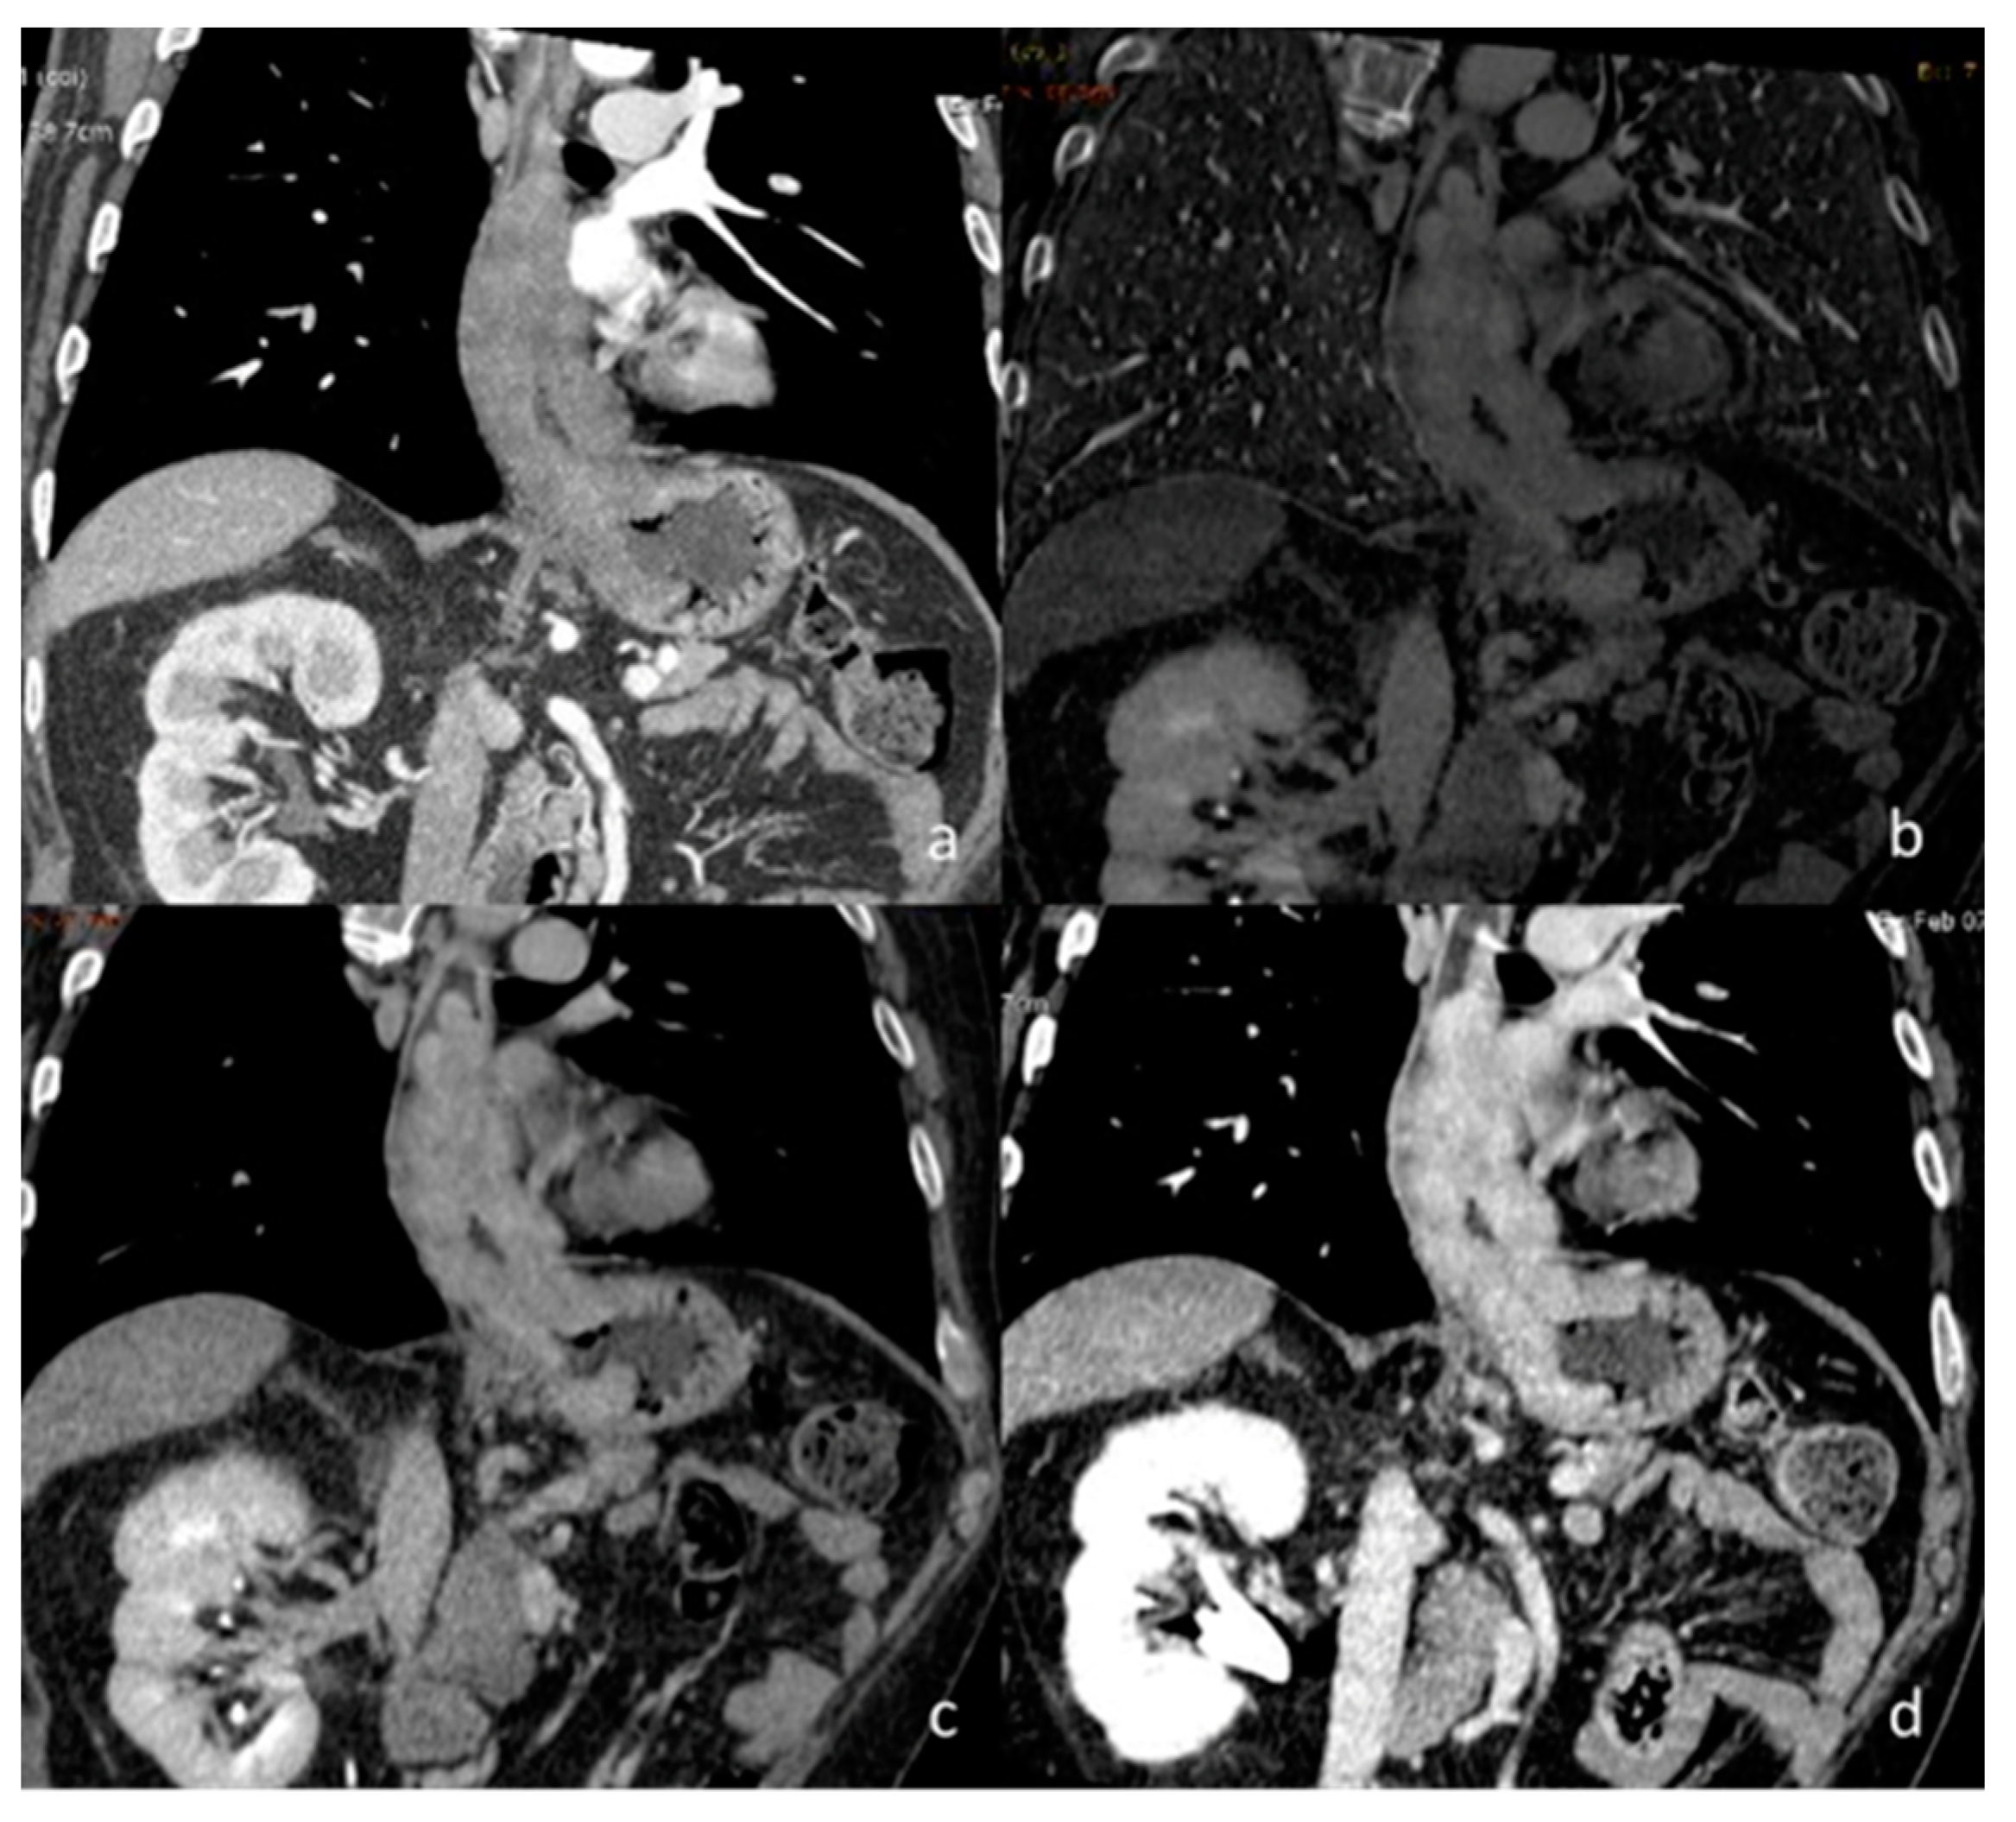

| Si-Mohamed et al. [67] Retrospective study | France | To assess whether VNC images derived from contrast dual-layer DECT images could replace TNC images for aortic intramural hematoma diagnosis in acute aortic syndrome imaging protocols by performing quantitative as well as qualitative phantom and clinical studies. | 21 | IQon, Philips Healthcare No C.I. | Dual-layer -DECT offers similar performances with VNC and TNC images for intramural hematoma diagnosis without compromise in diagnostic image quality. VNC imaging with dual-layer DECT reduces the number of acquisitions and radiation exposure in acute aortic syndrome imaging protocol. |